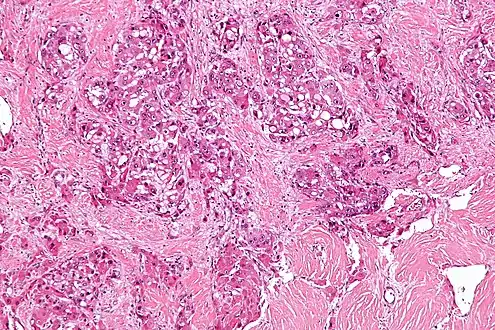

| Micrograph of fibrolamellar hepatocarcinoma showing the characteristic laminated fibrosis between the tumor cells with a low NC ratio. H&E stain. | |

The histopathology of FLC is characterized by laminated fibrous layers, interspersed between the tumor cells. Cytologically, the tumor cells have a low nuclear to cytoplasmic ratio with abundant eosinophilic cytoplasm.[1] Tumors are non-encapsulated, but well circumscribed, when compared to conventional HCC (which typically has an invasive border).

Intermed. mag.

High mag.